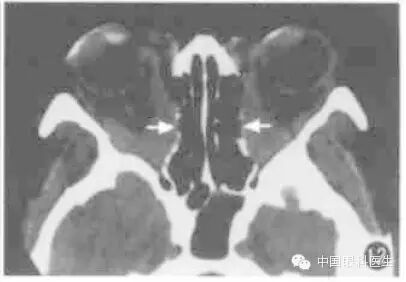

眶内静脉曲张常规CT扫描时多不显影,或仅显示小部分病变,欲观察病变全部范围可行颈部加压检查(图1,图2)。将血压计袋缠于患者颈部,摆好位置,加压至5.33kPa(高于静脉压),再行扫描检查,扫描完毕后立即将气囊放松。

图1左眶静脉曲张,平扫CT显示左眶后少许软组织密度(箭头)

图2同例静脉曲张加压后CT显示左眼球明显出土,球后出现巨大高密度软组织块影(箭头)